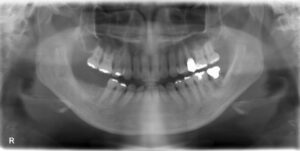

下顎臼歯5本欠損症例

BEFORE AFTER 61歳女性/下顎5本/インプラント埋込手術 【治療内容】 健診希望でご来院された患者さんです。…